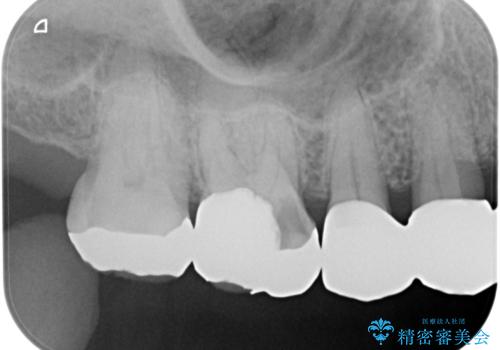

- メタルの詰め物がされている歯が欠けてしまった患者様です。

メタルを外すと中で虫歯が広がっていました。

拡大鏡下で虫歯を取り切った後、フルジルコニアクラウンにて治療しました。

メタルの詰め物や被せ物は歯質との間に隙間ができやすく虫歯の原因の細菌が侵入し、虫歯の再発に繋がります。